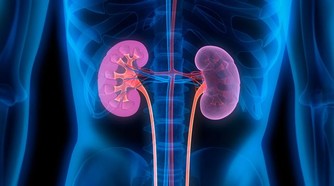

激素,包括含氮激素以及類固醇激素,長期使用可致陽氣極大地損傷;其作用於腎,可以把腎精中管我們壽命的陽氣釋放出來用;激素所動用的腎精本來是用來溫陽以養命的,濫用激素過分地消耗了腎精,隨之就會出現陽虛諸症,激素用得越久,陽氣損傷越嚴重,陽虛症狀更明顯。